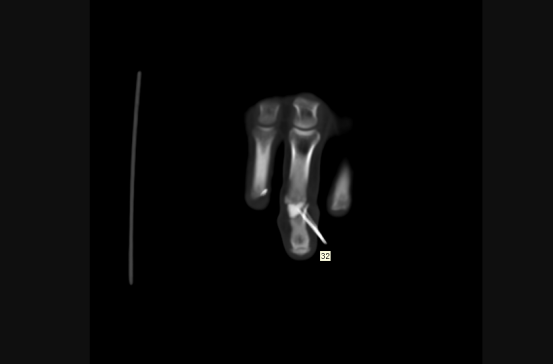

術后手指關節恢復良好

目前患者恢復良好,一段時間后,移植的關節便可和原本的關節完全一樣,沒有結構和功能差異。